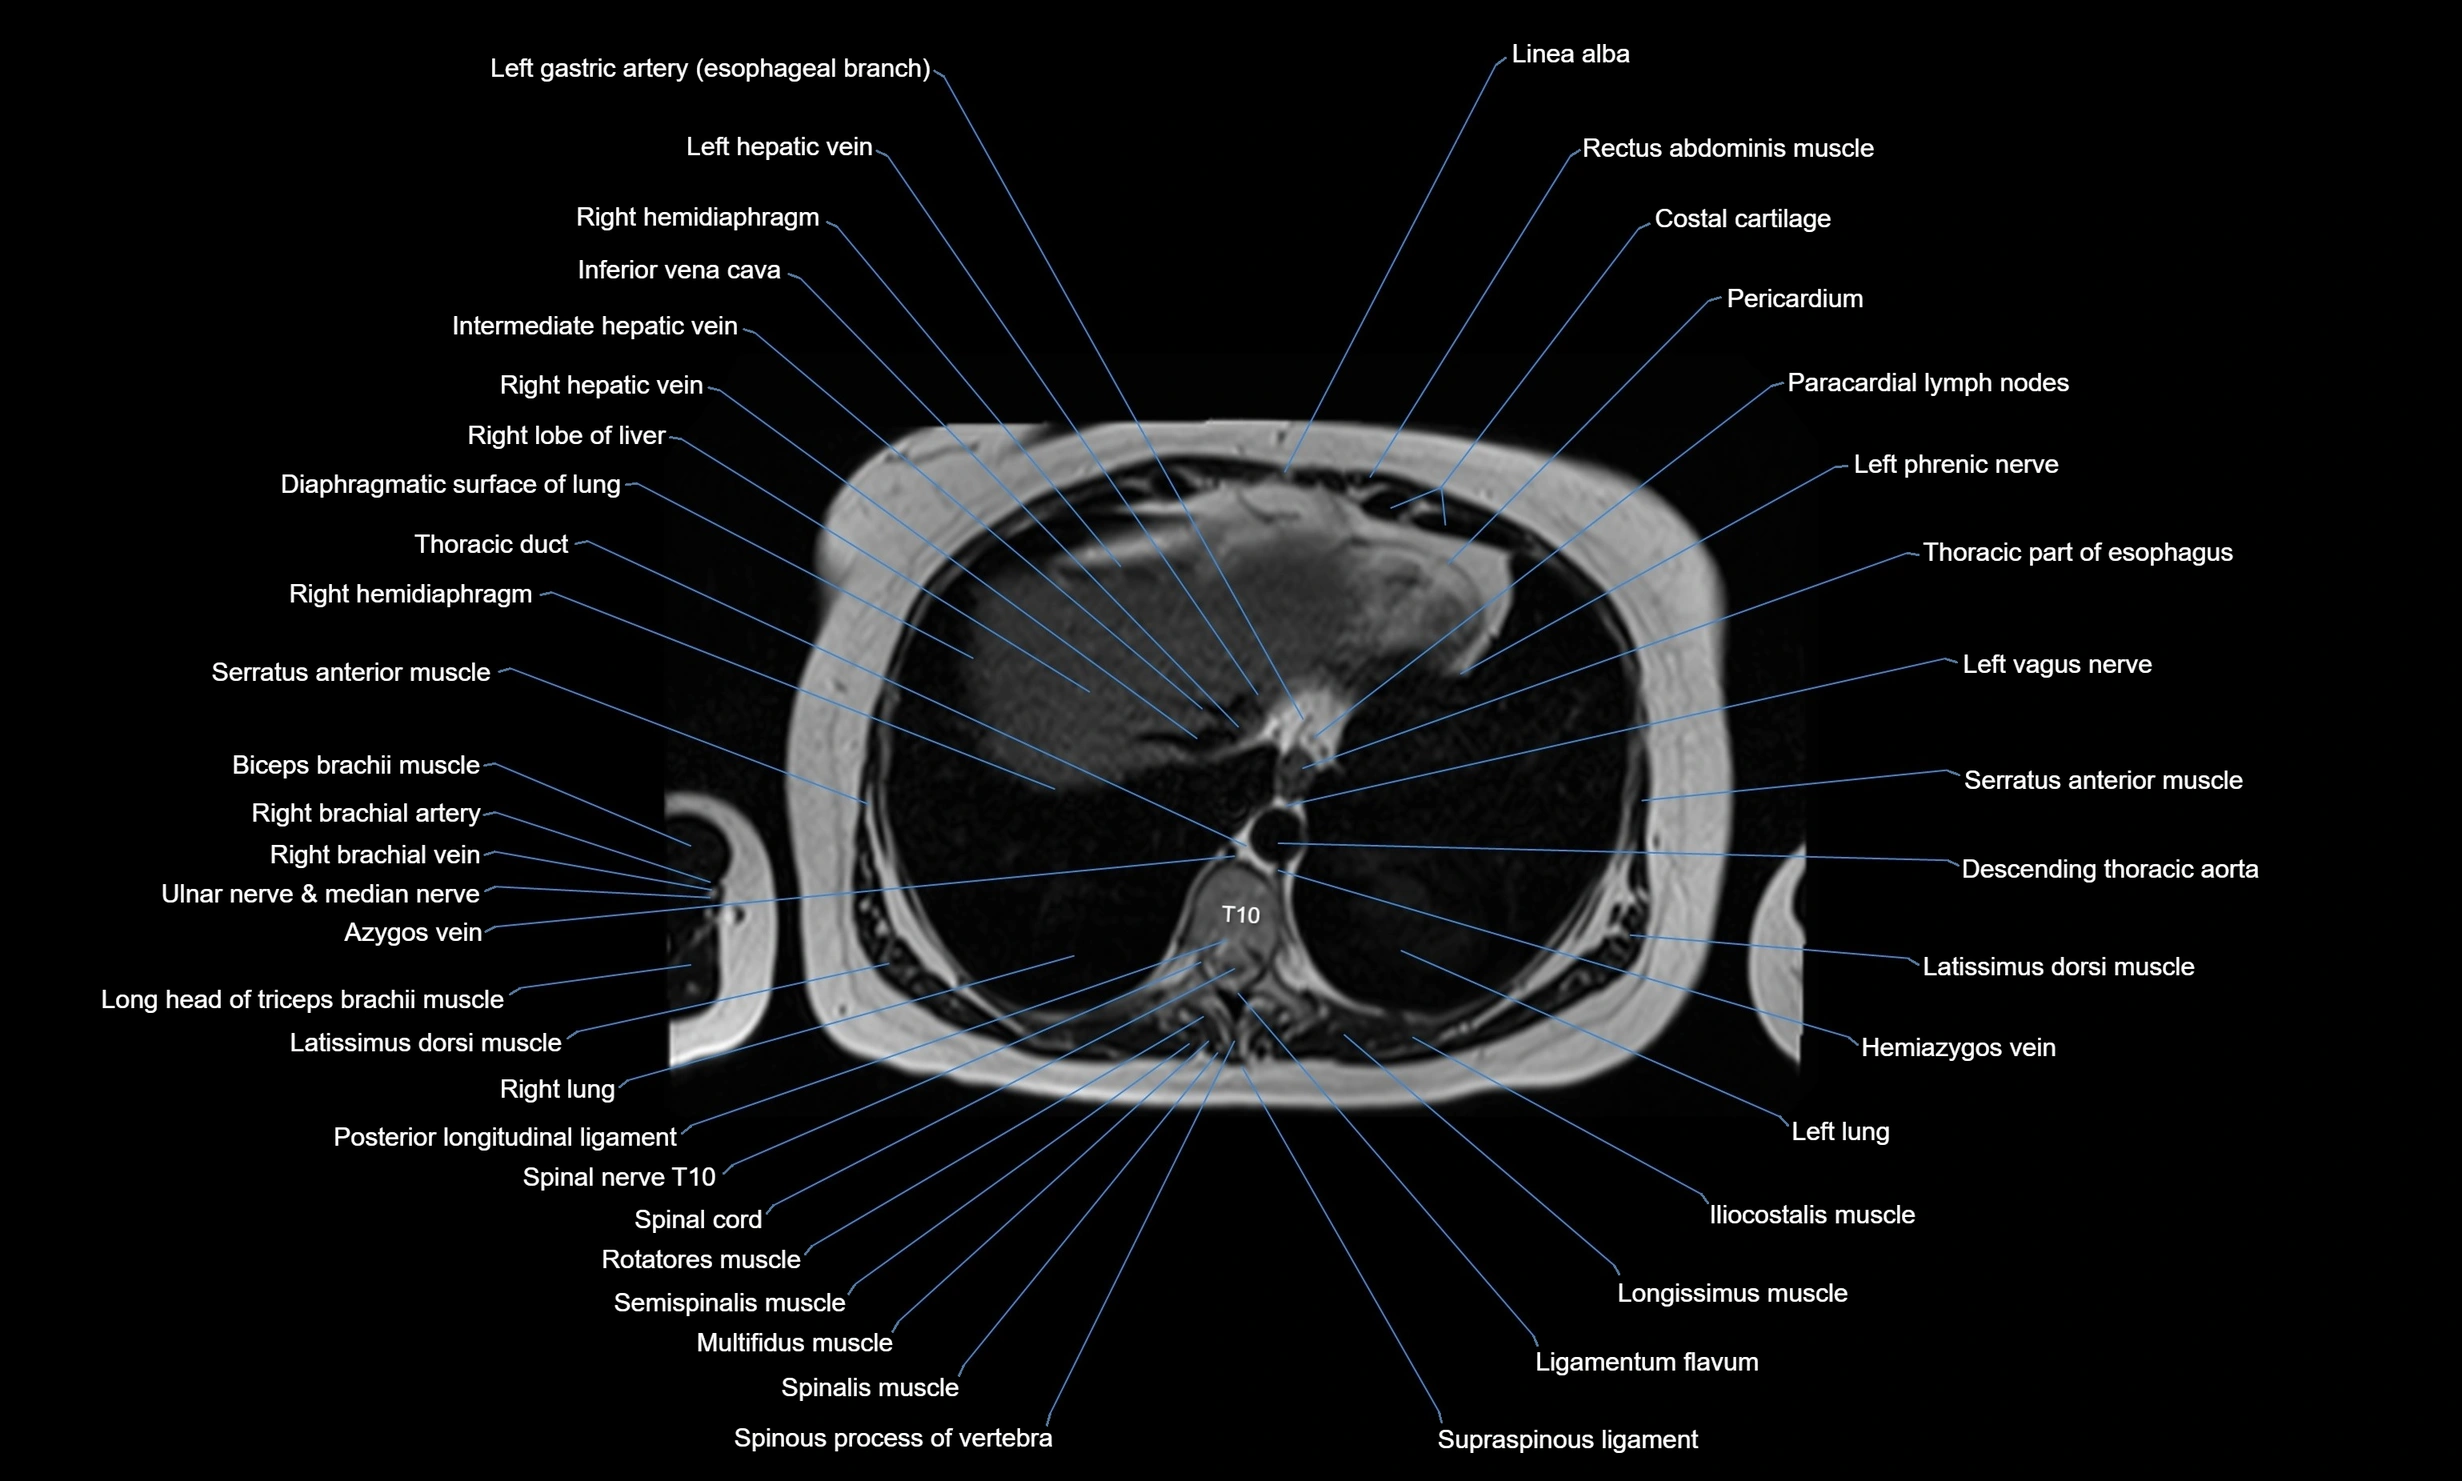

- Azygos vein

- Descending thoracic aorta

- Hemiazygos vein

- Inferior lobe of left lung

- Latissimus dorsi muscle

- Long head of triceps brachii muscle

- Right lung

- Rotatores muscle

- Serratus anterior muscle

- Spinal nerves

- Spinous process of vertebra

- Thoracic duct

- Thoracic part of esophagus